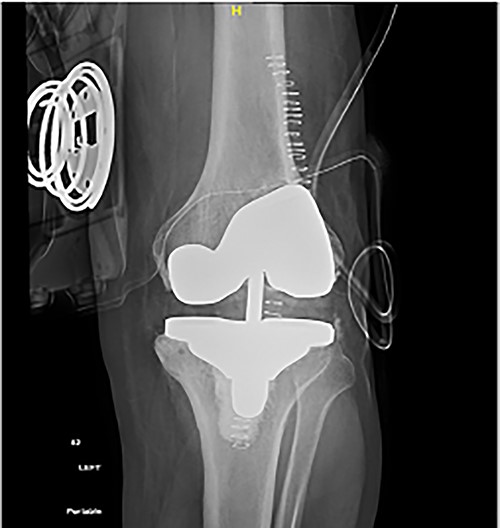

Following templating, the primary posterior stabilized Triathlon® and Total-stabilizer (TS) Triathlon® revision sets were made ready. The TKA was performed through the medial parapatellar approach. Quadriceps’ sparing techniques were avoided to reduce the chance of disrupting the prior tendon transfer. Femoral preparation was carried out first to make sure the distal femur deformity would not impede femoral component positioning. The decision as to whether to go with PS or TS Triathlon femoral components was based on the feasibility of the posterior femoral condyle cuts. The stem was inserted and then the cutting jig was placed. When checking the posterior and anterior cuts, it was noted that no bone would be cut from the posterior condyles using the TS Triathlon cutting block. Hence, the decision to use the primary PS cutting block was made without correcting the distal femoral extension deformity. Following the femoral cuts, tibial preparation was completed using the tibia TS knee system. A short stem of 50 mm was used intentionally due to his reasonably good bone and to allow for longer stems should the necessity arise in the future because of the patient’s young age and the high possibility of revision surgery in polio patients. In addition, this allowed for the use of semi-constrained polyethylene. The patella was found to have small 1-cm2 islands of cartilage, representing the medial and lateral facets. However, the rest of the patella was bare of cartilage. Patellar resurfacing was done to avoid anterior knee pain (Fig. 4).

Post-operative plain radiographs from follow-up visits; (A) 3-month post-operative AP radiograph showing implant in place with a lateral gap sized to be 3.2 cm; (B) 3-month post-operative lateral radiograph of the knee showing implant in a satisfactory position.